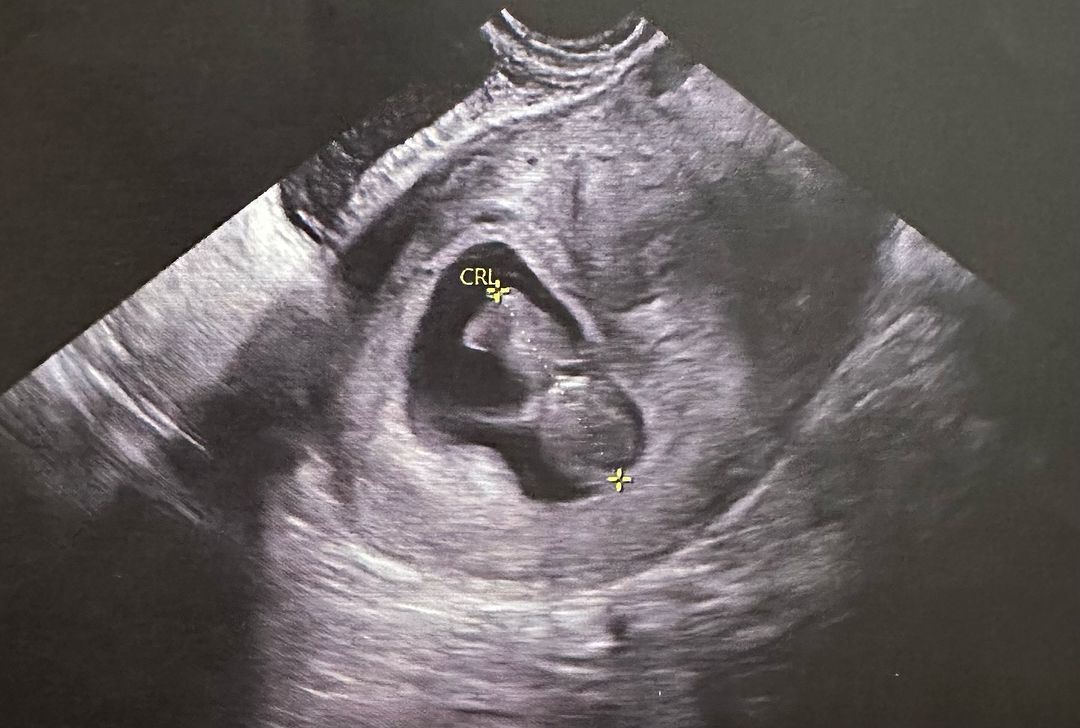

杨潮凯在社交媒体上晒出了超声波照,配文表示「我们又做爸爸妈妈啦!CatharineBB做家姐啦!」